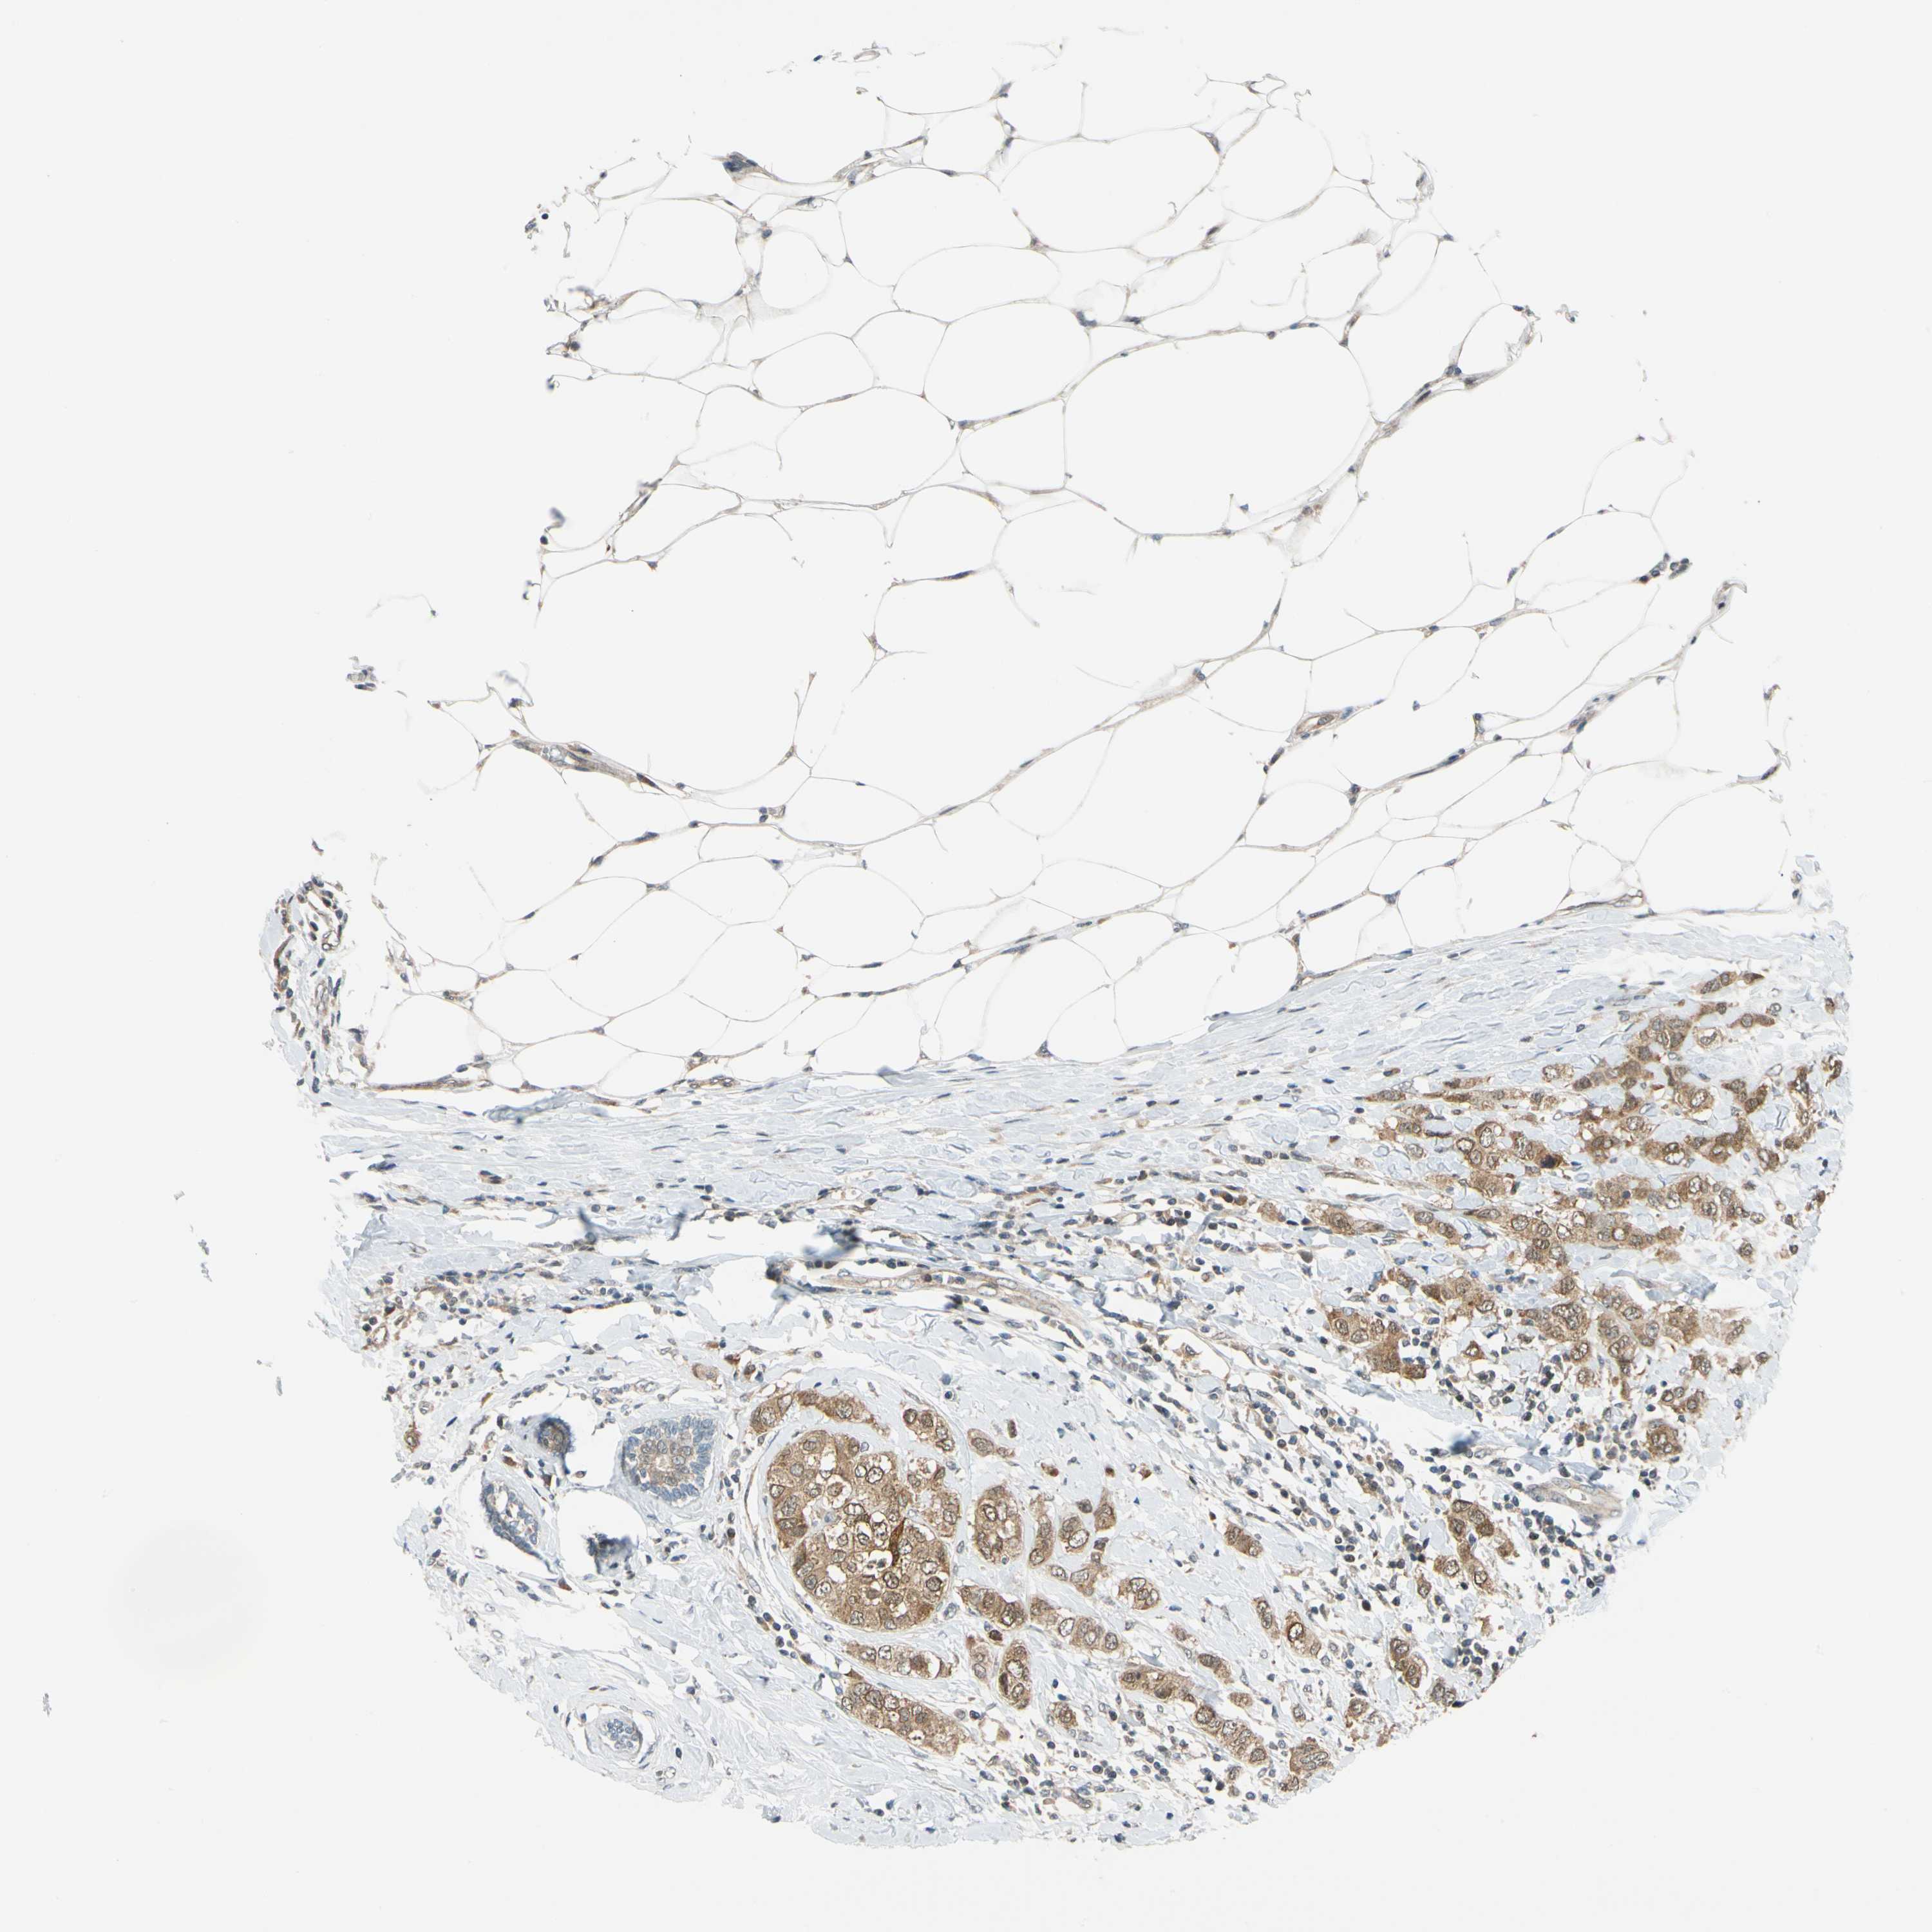

BRCA TCGA BRCA VALIDATION PROTEIN EXPRESSION